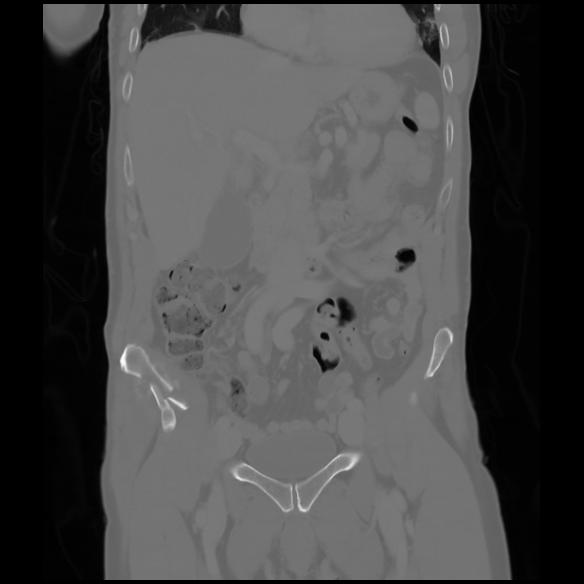

6 CUERPO,CE,Coronal,3.000,CUERPO,Coronal,